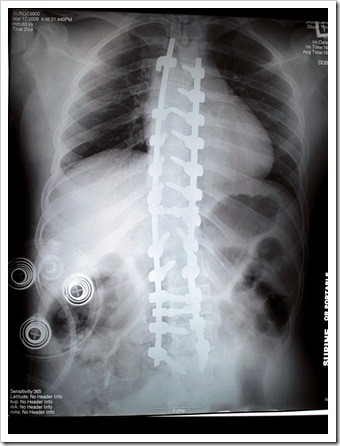

Most parent start by using the “wait and see what happens” approach. With many health conditions such as a cold or a flu this can be the best approach. However, if the type of scoliosis a child has is progressive allowing it to “run its course” will simply allow the condition to worsen. In severe cases this could ultimately lead to unsightly bracing or even surgery that attaches steel rods to the spine to force it into a straighter position.